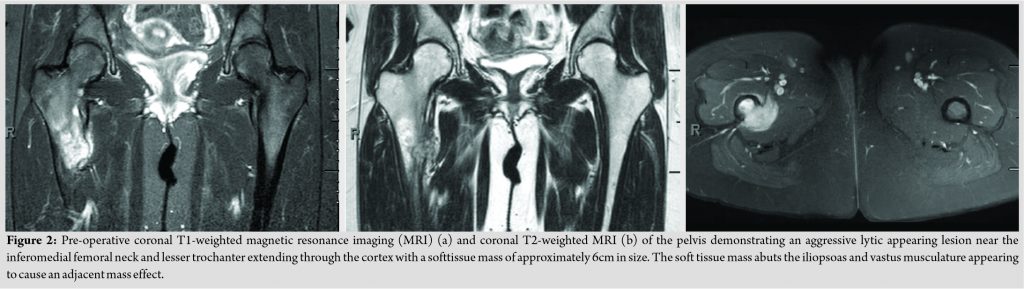

Radiographs were obtained by her primary care provider, which demonstrated a large, aggressive lesion with some mixed lytic and blastic features about the proximal femur (Fig. 1). On careful examination, there appeared to be a thin cortical rim over the margin of the lesion medially. Magnetic resonance imaging was obtained and demonstrated an aggressive appearing lesion centered near the inferomedial femoral neck as well as the lesser trochanter (Fig. 2). The lesion demonstrated a lytic appearance with some extension through the cortex. A soft tissue mass of approximately 6cm in size was present which abutted the iliopsoas and vastus musculature causing adjacent mass effect.